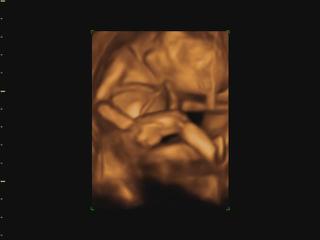

Ahojte babulky, tak dnes som bola na to 4D a cakame chlapceka, chcela som radsej dievcatko no no uz. Mam len video, tak ho nejak spracujem a hodim sem foto.